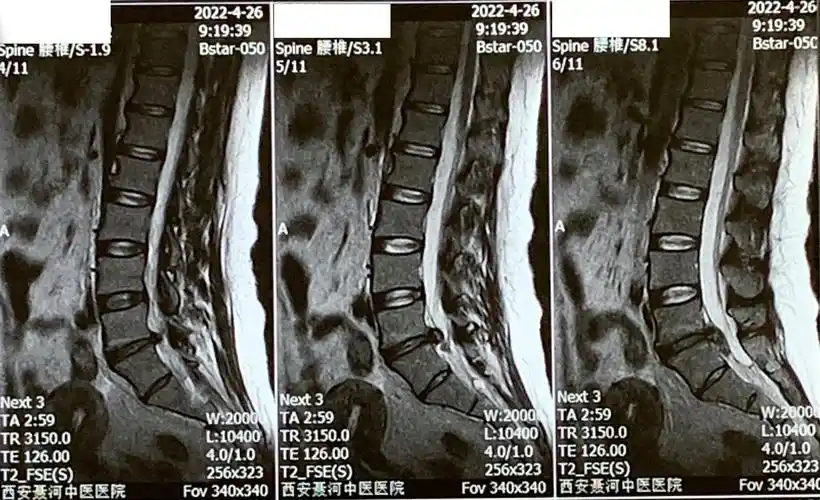

腰椎磁共振

患者术前的腰椎核磁共振片子.

20220426西安长安聂河中医院腰椎磁共振02.jpg